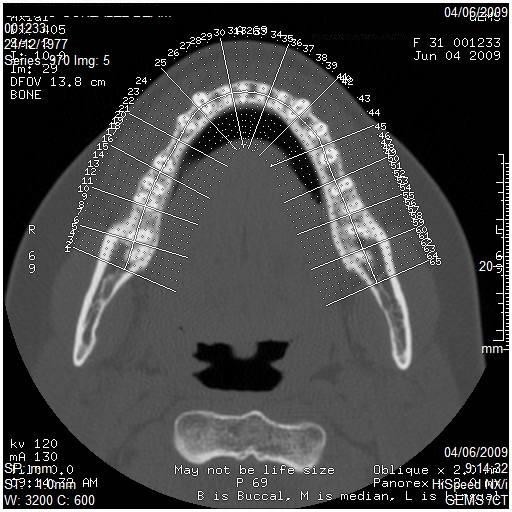

Los implantes óseo-integrados se han convertido en una forma aceptada de reemplazo dental permanente. Un importante avance en la evaluación preoperatoria de los candidatos para colocación de implantes es el desarrollo de un software para escanografia que es capaz de generar imágenes panorámicas y axiales del maxilar superior y de la mandíbula. Estas imágenes permiten al Odontólogo Implantólogo realizar varias medidas para determinar si el sitio es adecuado para la colocación de un implante.

Incluye la altura, ancho y angulación del reborde alveolar; calidad del hueso en el sitio del implante; relación del sitio del implante con las estructuras adyacentes como son el reborde alveolar, canal mandibular y foramen mentoneano en la mandíbula y el reborde alveolar, la fosa nasal, el seno maxilar y el ducto nasopalatino en el maxilar superior. La medición por escanografía es un método muy exacto de planeación permitiendo así una adecuada óseo integración del implante que ayuda al éxito del mismo.